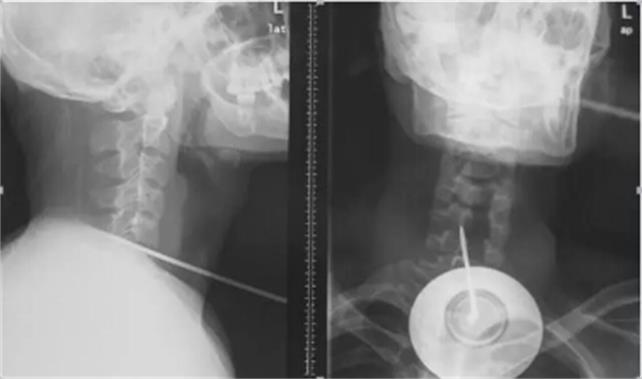

2月13日凌晨3時(shí),上海長(zhǎng)征醫(yī)院上演了一場(chǎng)真實(shí)版的“生死時(shí)速”。一根長(zhǎng)約17厘米的鋼針從患者頸部正中穿入氣管、食管,通過椎體,貫穿脊髓,直達(dá)后路椎板穿出,生命危在旦夕。海軍軍醫(yī)大學(xué)長(zhǎng)征醫(yī)院多科專家聯(lián)手合作,緊急手術(shù),展開了一場(chǎng)驚心動(dòng)魄的生死大援救,成功拔出了奪命鋼針。術(shù)后第二天,患者癱瘓的右側(cè)上下肢功能明顯恢復(fù)。

2月12日午夜時(shí)分,長(zhǎng)征醫(yī)院急診室接到120急救中心電話,有一名鋼針穿入頸椎,傷及氣管、食管,患者生命垂危。接到警情,急救科值班人員迅速開通搶救綠色通道,做好搶救措施。凌晨2時(shí),救護(hù)車風(fēng)馳電掣停在急診室門口。23歲的小陳,只身一人在上海打工,工作時(shí)意外跌倒,頸部刺入一長(zhǎng)約17厘米的鋼針。工友發(fā)現(xiàn)后將其送到上海一家大醫(yī)院,醫(yī)生認(rèn)為患者病情嚴(yán)重,建議立即轉(zhuǎn)診至全國(guó)脊柱外科技術(shù)實(shí)力強(qiáng)的醫(yī)院——海軍軍醫(yī)大學(xué)長(zhǎng)征醫(yī)院救治。

然而,手術(shù)麻醉成了******道難題。由于鋼針將氣管、食管、脊髓固定在椎體上,無法進(jìn)行麻醉插管,耳鼻咽喉科徐亞平醫(yī)生另辟蹊徑,從鋼針下游,切開氣管實(shí)施插管,避免出血進(jìn)入氣管引起窒息。隨后,麻醉科鄭棟煜迅速完成傷者全身麻醉。首先脊柱二科史建剛教授采用頸部右側(cè)切口,游離皮下間隙,進(jìn)入椎間間隙,只見氣管、食管椎間盤被鋼針貫穿,醫(yī)生細(xì)心顯露頸5、6椎間盤前部,在確保周圍頸部大動(dòng)脈不被鋼針損傷時(shí),以***快的速度拔除鋼針。突然發(fā)生了驚險(xiǎn)一幕,拔出鋼針后,大量的腦脊液和鮮血往外涌出,醫(yī)生迅速鉗夾控制出血,修補(bǔ)硬脊膜,并對(duì)損傷嚴(yán)重的頸部?jī)蓚€(gè)骨贅進(jìn)行切除,徹底減輕脊髓壓迫。隨后胸心外科陸昕冶醫(yī)生仔細(xì)尋找食管、氣管壁破損缺口,進(jìn)行了縫合修補(bǔ),止住了食管、氣管漏。經(jīng)過3小時(shí)“戰(zhàn)斗”,小陳終于闖過了“鬼門關(guān)”。

據(jù)主刀醫(yī)生史建剛教授介紹,頸部解剖復(fù)雜,有頸部血管、氣管、神經(jīng)、食道、咽喉等重要結(jié)構(gòu),嚴(yán)重頸部創(chuàng)傷在受傷后往往因大出血及窒息而死亡,搶救成功率低。迅速診斷、及時(shí)手術(shù)、密切監(jiān)護(hù)、精準(zhǔn)救治是搶救成功的關(guān)鍵。此次成功救治患者,充分展示了長(zhǎng)征醫(yī)院過硬的技術(shù)實(shí)力和強(qiáng)大的團(tuán)隊(duì)力量。